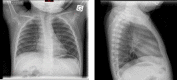

A 12-month-old boy, with no medical history, was admitted for dyspnoea with no cough or fever. Chest auscultation revealed an expiratory wheezing with decreased right-sided breath sounds. Chest imaging revealed subcarinal adenopathy and a nodule in the right principal bronchus (RB). Bronchoscopy showed a major obstruction of the RB by a granuloma, and a smaller granuloma in the left principal bronchus. The granulation tissue was removed by laser section. Histological examination revealed a necrotising granulomatous inflammation, culture showed a Mycobacterium avium complex (MAC). Tests to rule out tuberculosis and immunodeficiency were negative. The diagnosis of an MAC endobronchial granuloma was ascertained and a multidrug therapy associating clarithromycin, rifampin and ethambutol was started. The clinical outcome was good after 3 months of treatment and the bronchoscopy normalised after 1 year. Although rare, the frequency of MAC respiratory infections in immunocompetent children can increase. Reporting these cases should help to optimise diagnosis and treatment.